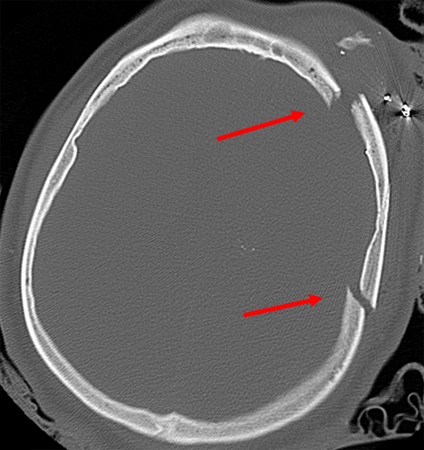

Skull fracture may be a presenting sign of child abuse, and this should be suspected if the social circumstances of injury are uncertain or of a suspicious nature. However, skull fractures are more prevalent in non-abuse, than abuse, in children younger than 2 years old. The most common type of fracture in both situations is a linear parietal fracture. Other signs of abuse that may be present include retinal haemorrhages, coexisting apnoea or another form of acute respiratory compromise, coexisting bruising to the head, neck or torso, or rib or long-bone fractures.[12][13][14] See Child abuse.[Figure caption and citation for the preceding image starts]: Linear parietal fracture without depression [Citation ends].

Fractures are also categorised according to location in the parietal and frontal portions of the cranium or in the temporal or occipital areas of the skull base. [Figure caption and citation for the preceding image starts]: Linear parietal fracture without depression [Citation ends].